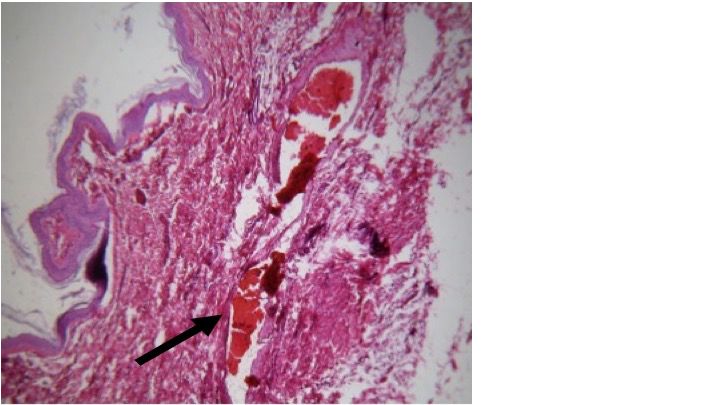

El Síndrome Compartimental Abdominal (SCA) y la Hipertensión Intraabdominal (HIA) son conocidos desde los estudios tempranos del Siglo XIX en Francia, como entidades patológicas que ponen en riesgo la vida derivado de graves eventos deletéreos afectando las extremidades o el abdomen, estructuras bien delimitadas por las fascias o bien cavidades óseas que inesperadamente sufren un aumento drástico de su presión interna. El objetivo de este trabajo fue investigar las notables analogías morfofisiopatológicas que caracterizan a esta condición, y correlacionarlas como base diagnóstica contra dos casos clínicos espontáneos de SCA observados en cerdos híbridos de la raza Landrace-Yorkshire de 5 meses de edad, que posterior a sus intervenciones quirúrgicas muriesen en forma hiperaguda por asfixia con datos de tipo Síndrome Policompartimental (SPC).   A la inspección clínica inicial se observó eritema facial diseminado, extensa hemorragia subconjuntival, epistaxis, marcada distensión abdominal con dehiscencia de la herida quirúrgica previa y evisceración masiva en un caso, así como moderada en el segundo animal, presentando ambos sujetos prolapso rectal y aparente necrosis de mucosa. Los hallazgos de histopatología revelaron cambios multiorgánicos focales pero graves afectando órganos internos con isquemia, dilatación y congestión. Se postula que debido a la asfixia repentina y la naturaleza hiperaguda de las lesiones encontradas, ello explica una disfunción multiorgánica circunspecta consistente con hallazgos de casos descritos de SPC tanto en modelos animales inducidos como en casos graves de eventualidades humanas. Finalmente, se postula que esta investigación analógica ilustró cómo un caso espontáneo de SPC cumplió con criterios diagnósticos internacionalmente aceptados para esta condición humana, representando en el caso del cerdo un modelo animal inducido asequible que permitirá enriquecer la investigación del SPC, una rareza que a nuestro juicio nunca se había reportado como ocurrencia espontánea en un animal de laboratorio.